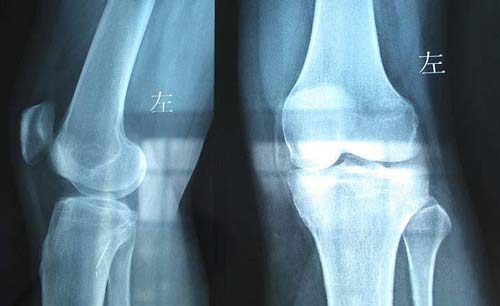

(图:患者膝关节骨质增生,关节疼痛不能下地)

(图:患者治疗后双膝关节骨质恢复正常)